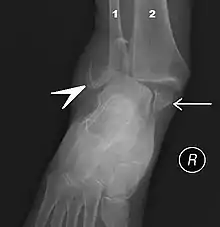

التصوير بالأشعة السينية

يمكن أن يظهر الكسر على الصورة السينية في الكعب الإنسي أو في الكعب الوحشي أو في الحافّة الأمامية أو الخلفية للجزء القاصي من الظنبوب. إذا تم كسر كل من الكعبين الوحشي والإنسي، يسمى ذلك بكسر الكعبين. إذا كُسر الكعب الخلفي أيضاً، يسمى ذلك بالكسر الكعبي الثلاثي.